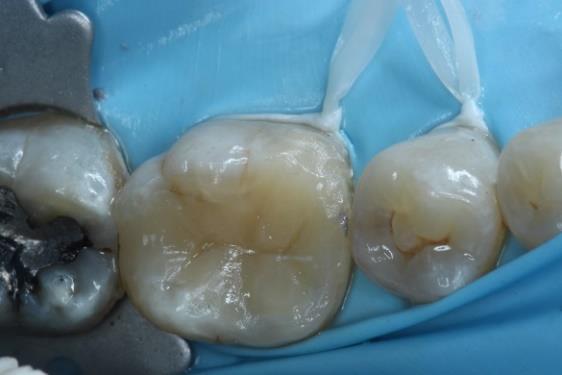

Dr. Dhiraj Arora: A Simple Sequence for Successful Root Canal Treatment Outcomes (EN)